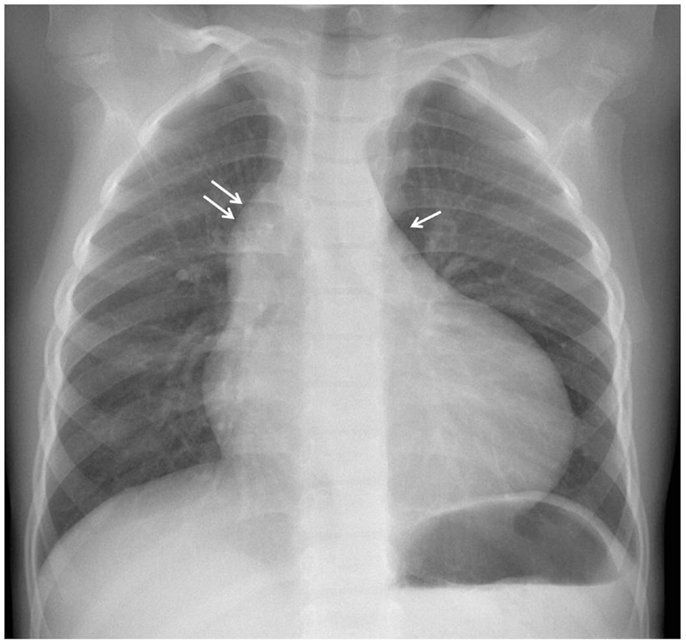

Heart borders on a CXR

How to identify pulmonary trunk on CXR?

ABove the left main bronchus but below the aortic knuckle